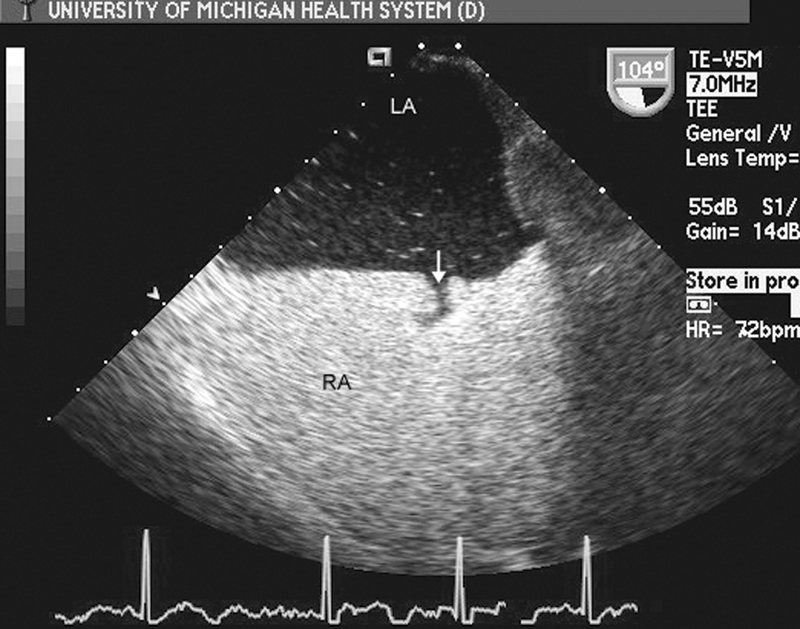

فحوصات تشخيصية لبعض امراض القلب والشرايين التاجية